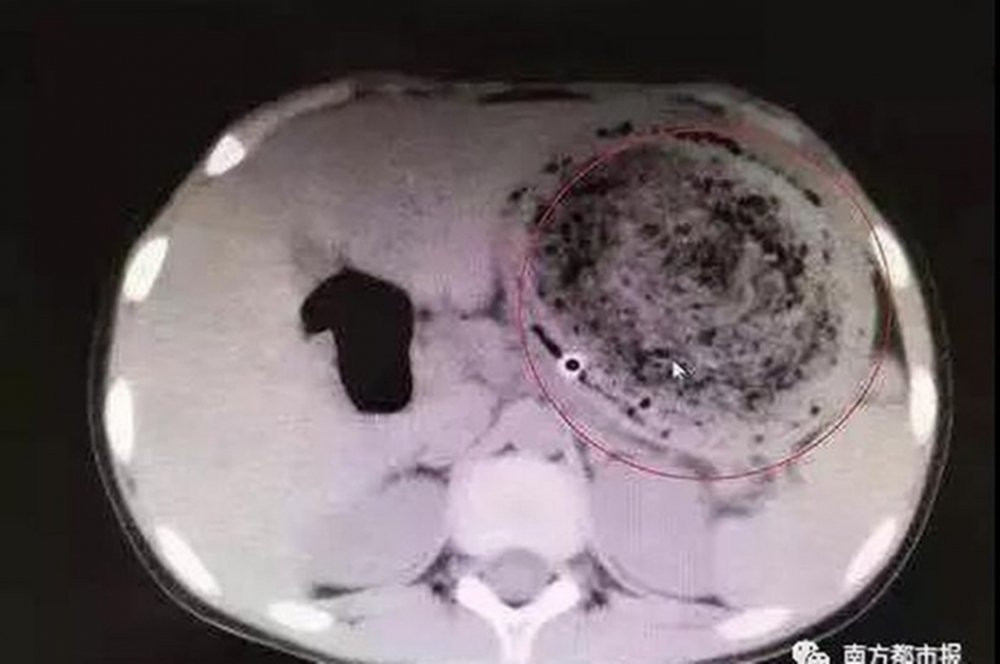

Kết quả siêu âm cho thấy trong dạ dày của Feifei chứa một búi tóc lớn, cuộn rối với nhiều cặn thức ăn.

Tại đây, Feifei được rửa dạ dày nhưng bác sĩ không tìm thấy dư lượng thực phẩm nào mà là một búi tóc rối rất lớn cuộn với cặn thức ăn. Tuy nhiên, không thể loại bỏ được nó thông qua nội soi vì đã có dấu hiệu vôi hóa. Bác sĩ đã phải thực hiện phẫu thuật mổ dạ dày để có thể lấy búi tóc nặng đến gần 1,5kg ra khỏi bụng cô bé.